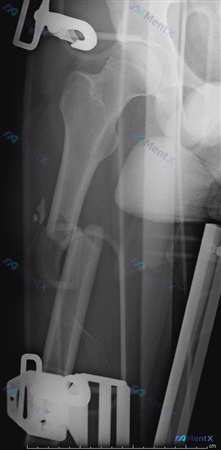

患者信息:22 岁男性

主诉:股骨损伤

影像表现:

- 右侧股骨干中上段粉碎性骨折,骨结构连续性中断

- 骨折断端明显移位及重叠,远端向近端移位,短缩畸形

- 近端股骨结构相对完整,未见关节内骨折线

- 可见金属外固定支架组件投影,处于外固定治疗状态